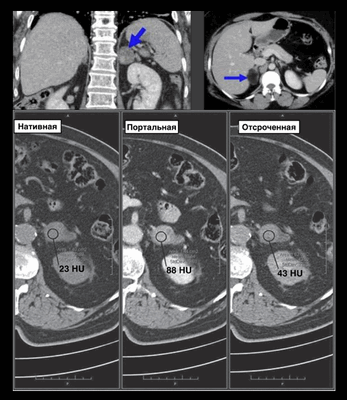

- Бесконтрастная КТ: менее 10 HU (чувствительность - 71%, специфичность - 98%)

о Аденомы с низким содержанием липидов (10-40% случаев): для диагностики используют оценку относительного или абсолютного вымывания контрастного вещества на КТ

1. КТ-протокол для визуализации надпочечников. Проведение бесконтрастной КТ часто бывает достаточным для диагностики аденомы коры надпочечников, которая выглядит в виде узелка гомогенной низкой плотности (менее 10 HU). Если патологический очаг не определяют или выявляют только при контрастном исследовании, определяют контрастирование образования, а затем повторно выполняют серию тонких срезов через надпочечники и измеряют относительную или абсолютную задержку вымывания контраста.

Большинство аденом содержит большое количество внутриклеточного и внеклеточного жира, который обусловливает характерное проявление в виде гомогенной плотности, близкой к водной (от -5 до +10 HU) на бесконтрастной КТ. Аденомы, содержащие большое количество жира, имеют такие же характерные признаки и на МРТ. Лучший метод визуализации для меньшей части аденом надпочечника, содержащих низкое количество жира, - «надпочечниковый протокол» КТ. Аденомы отличаются от метастазов и большинства других опухолей надпочечника характерным симптомом «вымывания» контраста - быстрое возвращение к исходному уровню контрастирования после внутривенного введения контрастного вещества.

(Слева) При образованиях надпочечника, не идентифицированных (более 70 HU) на бесконтрасной КТ, может быть выполнена оценка процента вымывания контраста на КТ надпочечников для выявления скрытых аденом с низким содержанием жира. На рисунке изображена формула определения процента вымывания контраста на КТ. Для расчета доступны веб-калькуляторы.

(Справа) Показан КТ-протокол для визуализации надпочечников. На бесконтрастной КТ (А) выявлено образование надпочечника с плотностью 30 HU. На КТ с контрастированием (Б) образование имеет плотность 60 HU, на отсроченной КТ (В) — 40 HU. Абсолютный процент вымывания контраста, составляющий 67%, служит характерным признаком аденомы с низким содержанием жира. (Слева) Схема алгоритма визуализации случайно выявленных образований надпочечника. Большое значение имеют история заболевания и предшествующие исследования. Большинство образований надпочечника-доброкачественные, однако диагностика может иметь решающее значение у пациентов с онкологическими заболеваниями. К/Н -контрольное наблюдение.